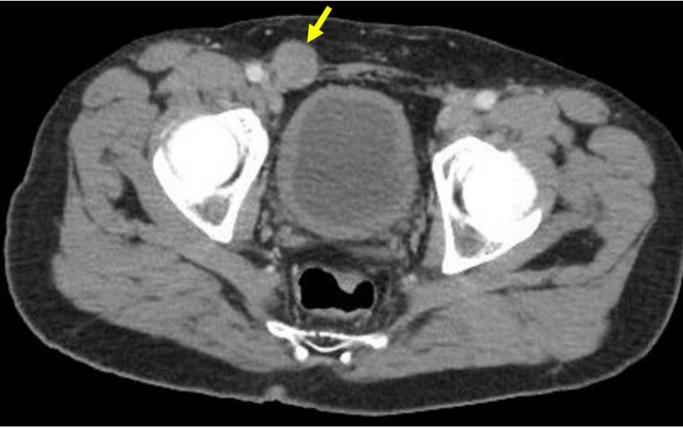

Paratesticular leiomyosarcoma is a rare malignant tumor deriving from the smooth muscle of structures surrounding the testes, including the epididymis or scrotum. With few cases of genitourinary soft tissue sarcomas reported in the literature, little is known about progression, management, and treatment. Herein, we report a case of metastatic paratesticular leiomyosarcoma in a 47-year-old male with no past urological history. The patient initially presented with a firm, painless right scrotal mass, and ultimately developed soft tissue and pulmonary metastases.

睾丸旁平滑肌肉瘤是一种罕见的恶性肿瘤,起源于睾丸周围结构(包括附睾或阴囊)的平滑肌。由于文献中报道的泌尿生殖系统软组织肉瘤病例较少,对于其进展、管理和治疗知之甚少。在此,我们报告一例47岁男性转移性睾丸旁平滑肌肉瘤病例,该患者既往无泌尿系统病史。患者最初表现为右侧阴囊质地坚硬、无痛性肿块,最终出现软组织和肺转移。